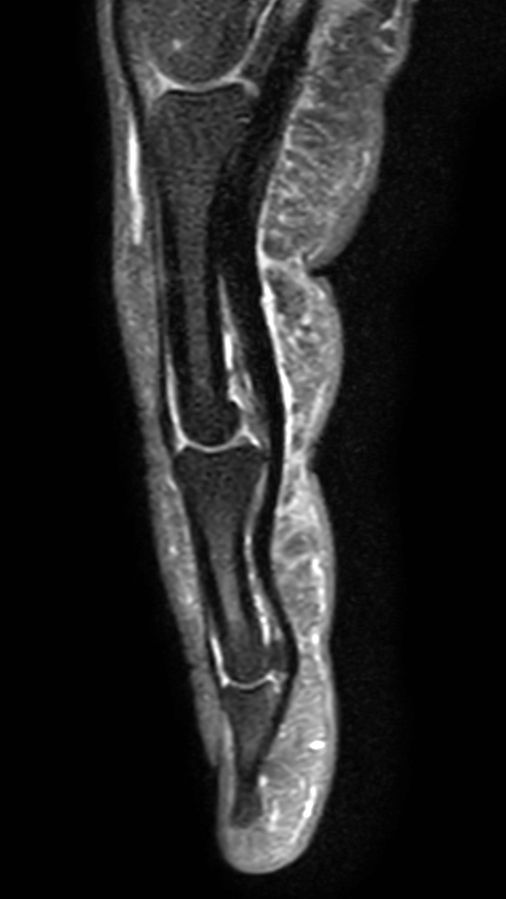

Coronal T1w TSE

Sagittal T1w TSE

Sagittal T2w TSE mDIXON XD

Sagittal PDw FatSat

Sagittal mFFE (cumulative)